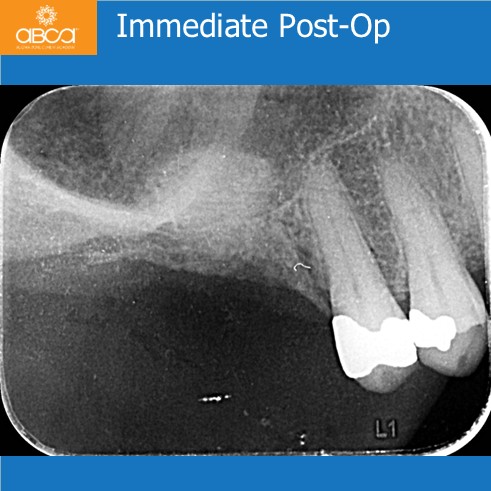

Categories3-6 Months, Augma Bone Cement Academy, Augma Lift™, Bond Apatite®, Bone Cement Expert, Clinical Cases, Closed Sinus Lift, Images, Kit A, Post-Op Period, Sinus Lift, Upper Right Molar March 2, 2026 Sinus Lift with Augma Lift™ Kit A – Missing Tooth #16 (3) Less than 2 mm of sub-sinus bone height Post navigationPrev Rehabilitation of the Left Maxilla, with Immediate Implant Placement Next Augma Simplified Webinar Leave a Reply Cancel replyYou must be logged in to post a comment.